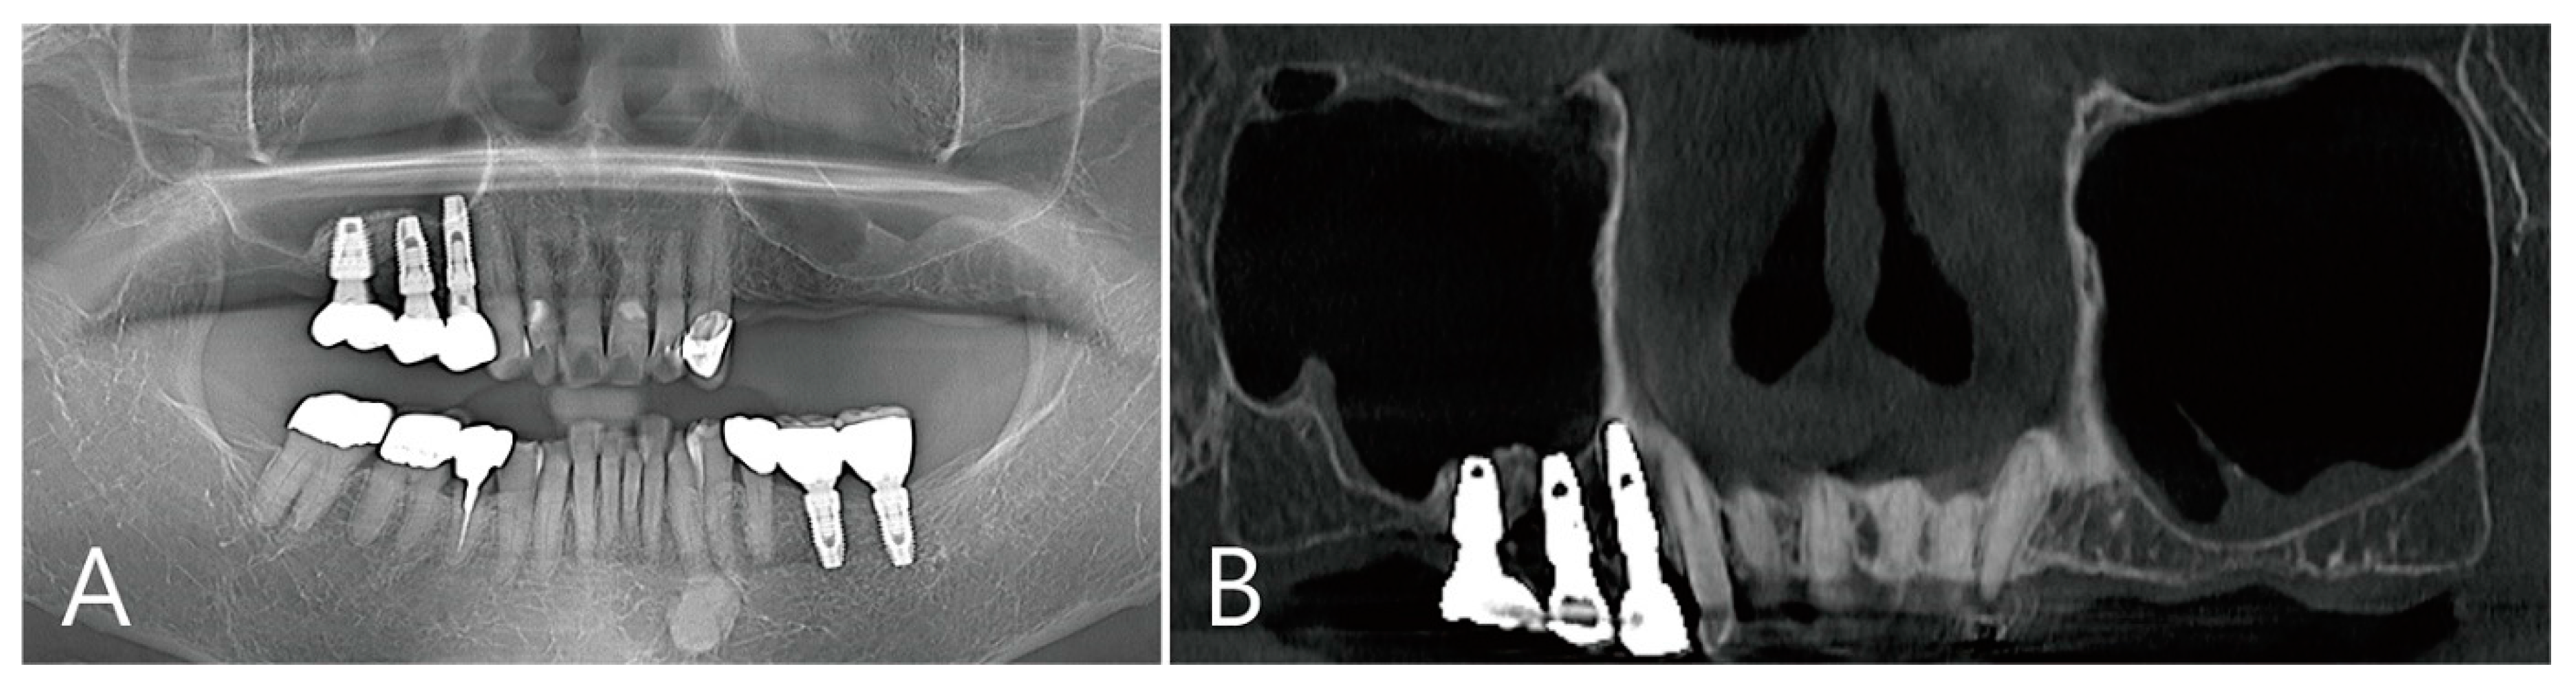

The coronal image of the CBCT scanned at the #27 implant site was examined. In the image taken immediately after surgery there was no leakage of bone graft particles (Figure 13A), however, a very large grafting void appeared in the image taken one week after surgery (Figure 13B). This grafting void showed a cystic appearance at the implant apex, although its size was reduced on CBCT taken after six months (Figure 13C). On the CBCT taken two years after the grafting void was removed, the grafting void was replaced with new bone (Figure 13D).

Figure 13. The coronal image of the CBCT scanned at the #27 implant site was examined: (A) in the image taken immediately after surgery, there was no leakage of bone graft particles; (B) however, a very large grafting void appeared in the image taken one week after surgery; (C) this grafting void showed a cystic appearance in the implant apex, although its size was reduced on CBCT taken after 6 months; (D) in CBCT taken 2 years after the grafting void was removed, the grafting void was replaced with new bone.